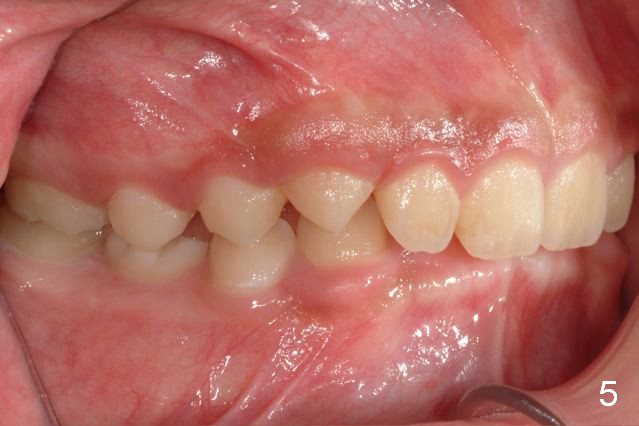

A 11-year-old boy has shorter lower 1/3 face (Fig.1,2) with light concave profile, especially the lower lip (Fig.3).  There is anterior deep bite (Fig.4) with Class II posterior occlusion (Fig.5,6).  UL2 is microdontia (Fig.7 *), while the Lower Es are retained (Fig.8).  Preop (2015_01_07) Ceph (Fig.9) and Pan (Fig.10) show ectopic L7s and congenitally missing L5s.